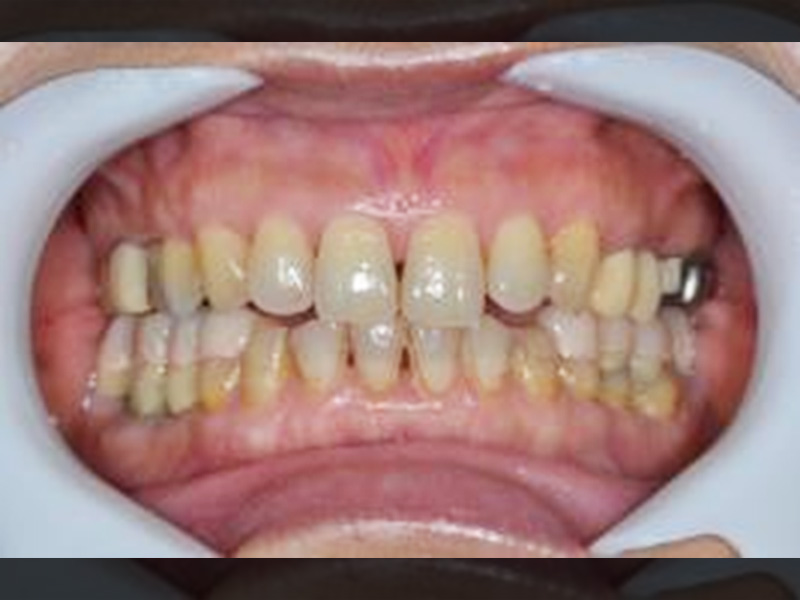

治療前の口腔内写真